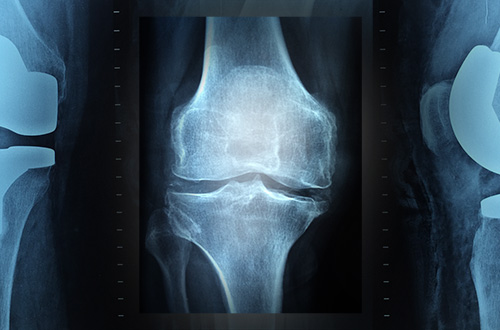

Osteoporosis merupakan gabungan dari dua kata, yaitu “osteo” yang dalam bahas Yunani berarti tulang dan “porosis” yang berarti keropos. Jadi sejatinya osteoporosis bukan merupakan suatu diagnosa penyakit, namun merupakan kumpulan gejala yang mengarah pada tulang keropos. Seperti halnya kayu yang keropos, tulang yang terkena osteoporosis akan lebih mudah patah.

Sebelum gejala tersebut muncul, dokter Franky menyarankan agar orang dengan usia lanjut atau diatas 40 tahun melakukan pemeriksaan kepadatan tulang atau Bone Mineral Density (BMD). Pemeriksaan ini dilakukan dengan menggunakan mesin dual-energy X-ray absorptiometry (DEXA).